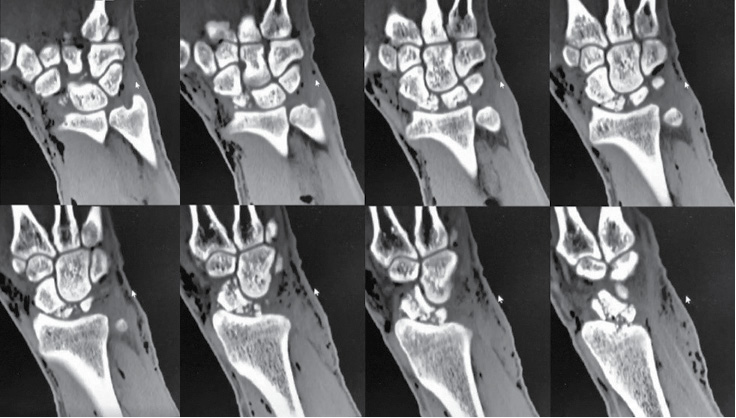

Skubiai atlikus riešo sąnario kompiuterinę tomografiją, nustatytas skeveldrinis laivelio proksimalinio galo lūžis, stipinkaulio distalinio dorzalinio krašto intrasąnarinis lūžis ir smulki mėnulio avulsija (žr. 1 pav.).

1 pav. Kairiojo riešo kompiuterinės tomografijos vaizdai prieš operaciją